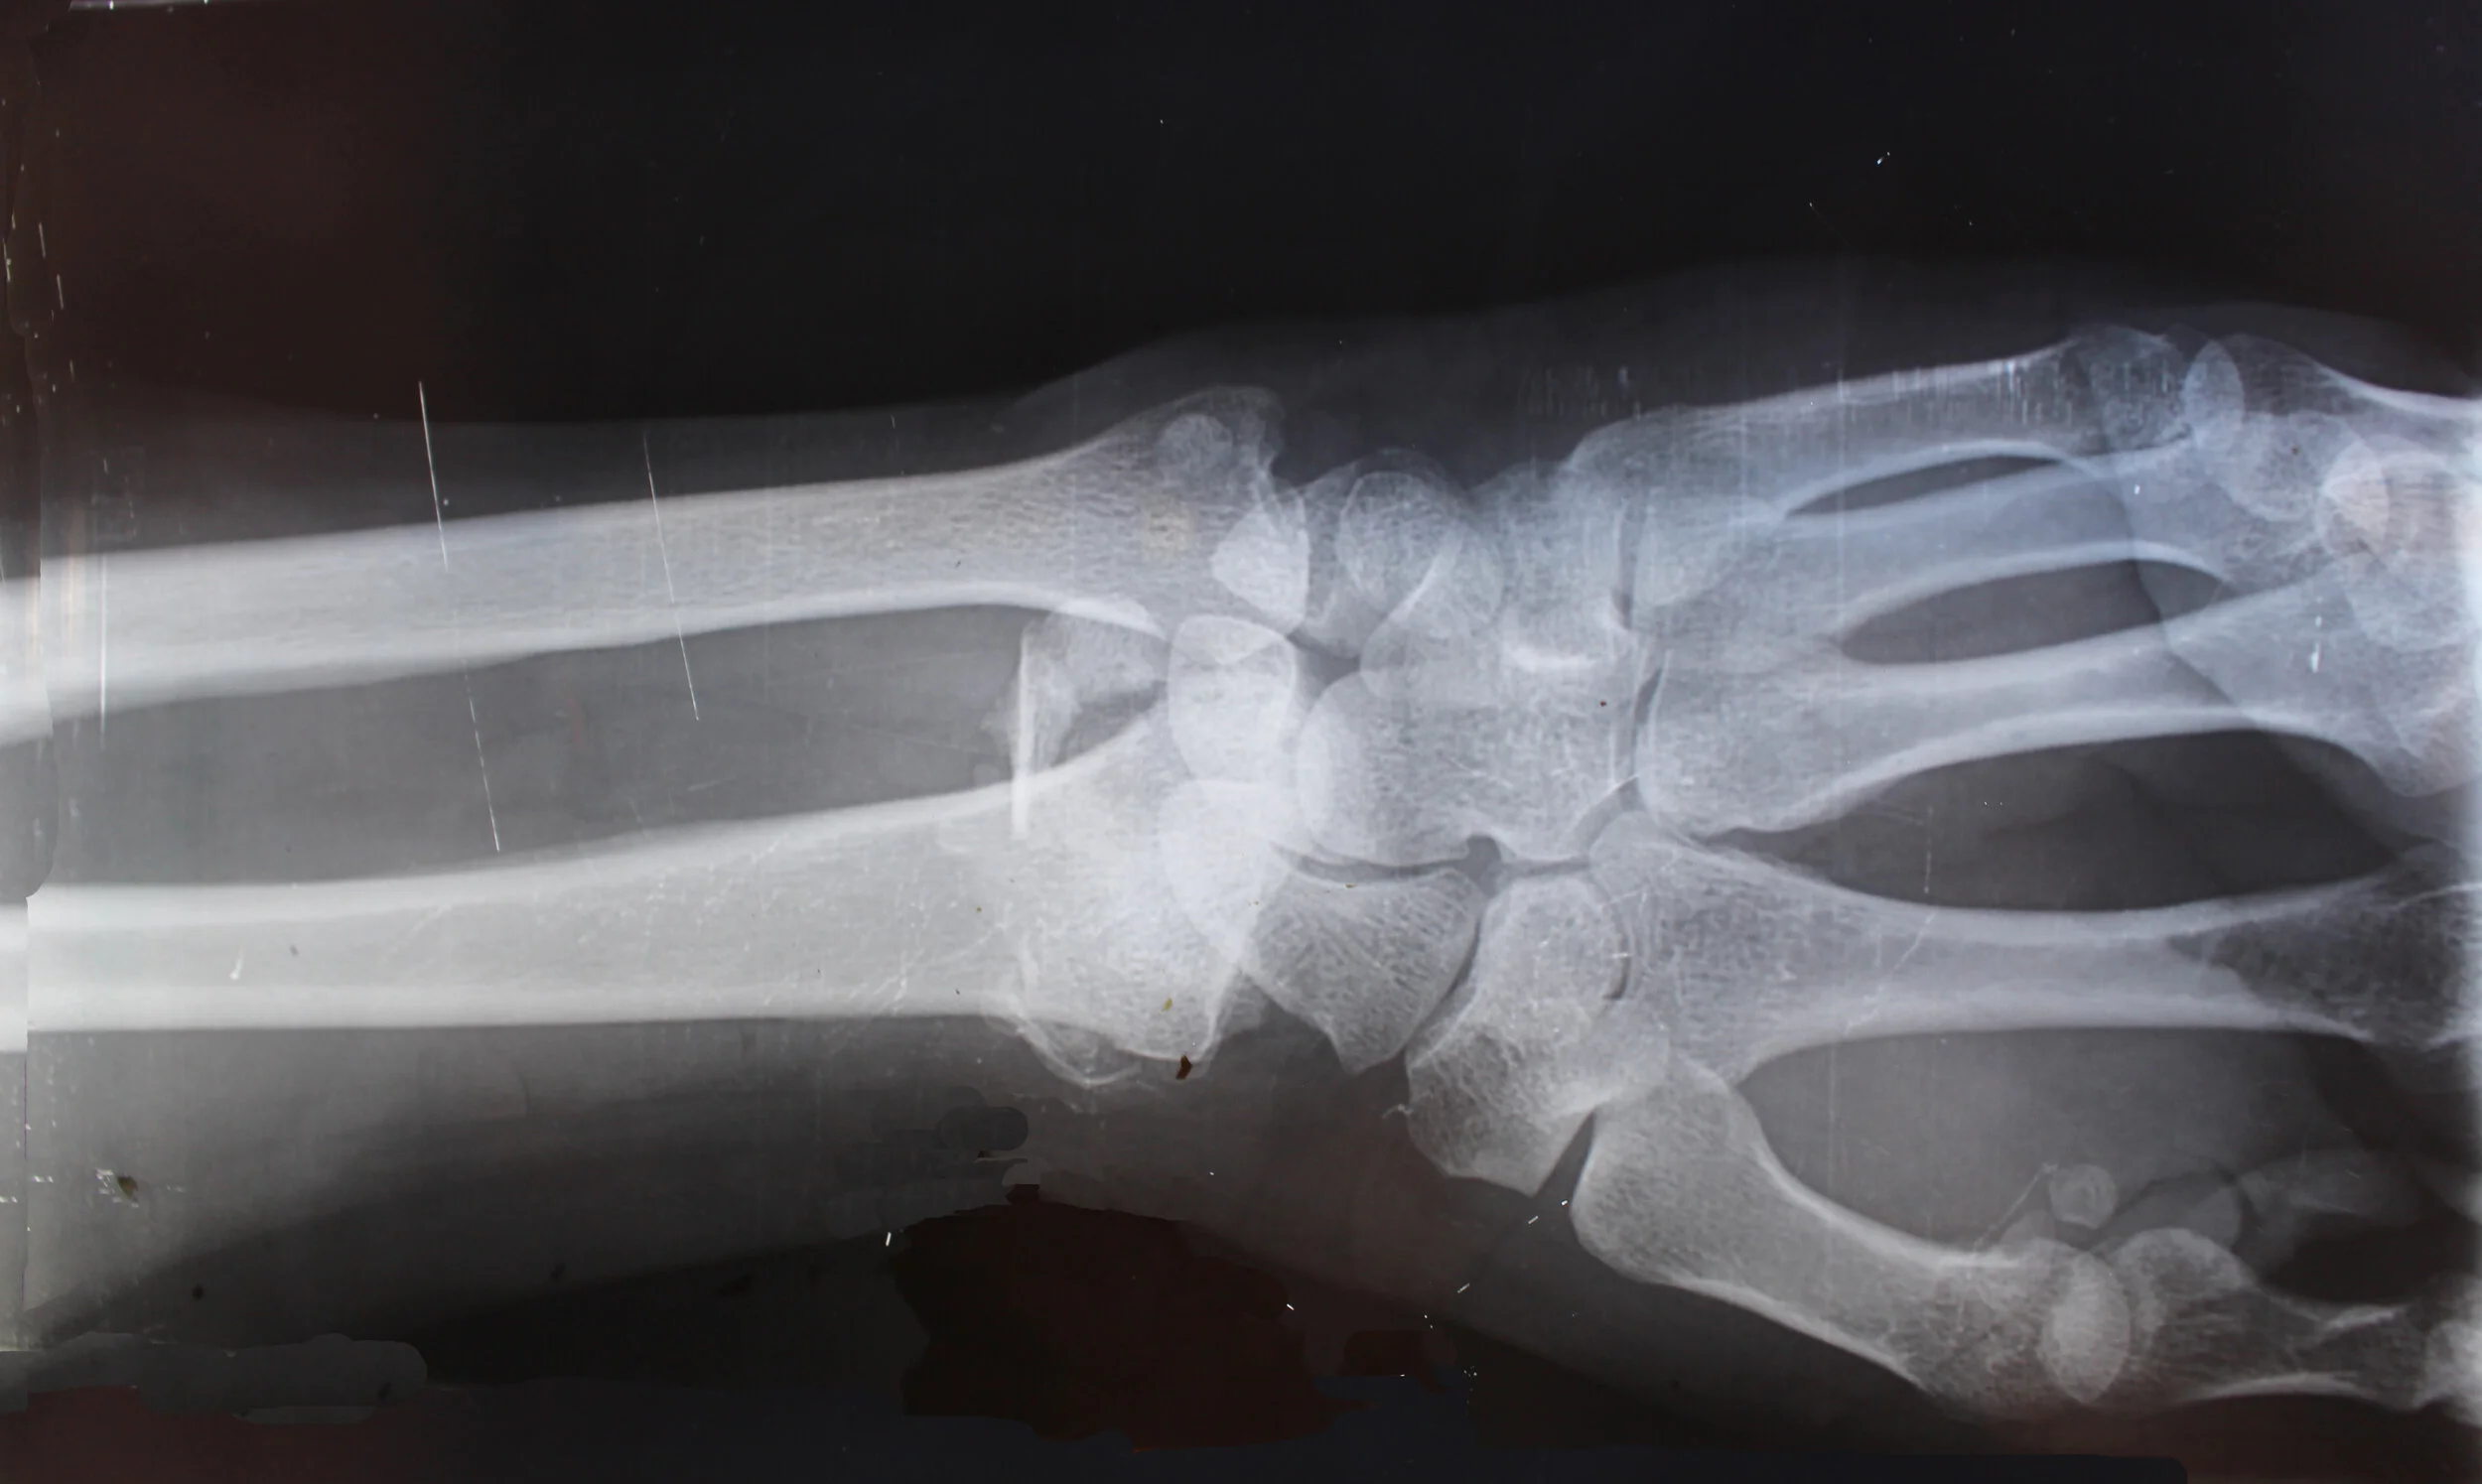

Bone Fractures: Types, Treatment & Symptoms

Types of Broken Bones: Symptoms, Treatment, Healing & Surgery

When you break a bone, healthcare providers call it a bone fracture . This break changes the shape of the bone . These breaks may happen straight across a bone or along its length . A fracture can split a bone in two or leave it in several pieces .

Fractures, broken bonesβyou can call it what you wish, they mean the same thing βare among the most common orthopedic problems; about 7 .9 million broken bones come to medical attention each year in the United States . 1 ο»Ώο»Ώ Despite what you may have heard, a broken bone is not worse than a fracture: They both mean the same thing .

A fracture occurs when a bone is struck by something stronger than the bone itself . This causes it to break . Car accidents, sports injuries, and falls are common causes of fractures .